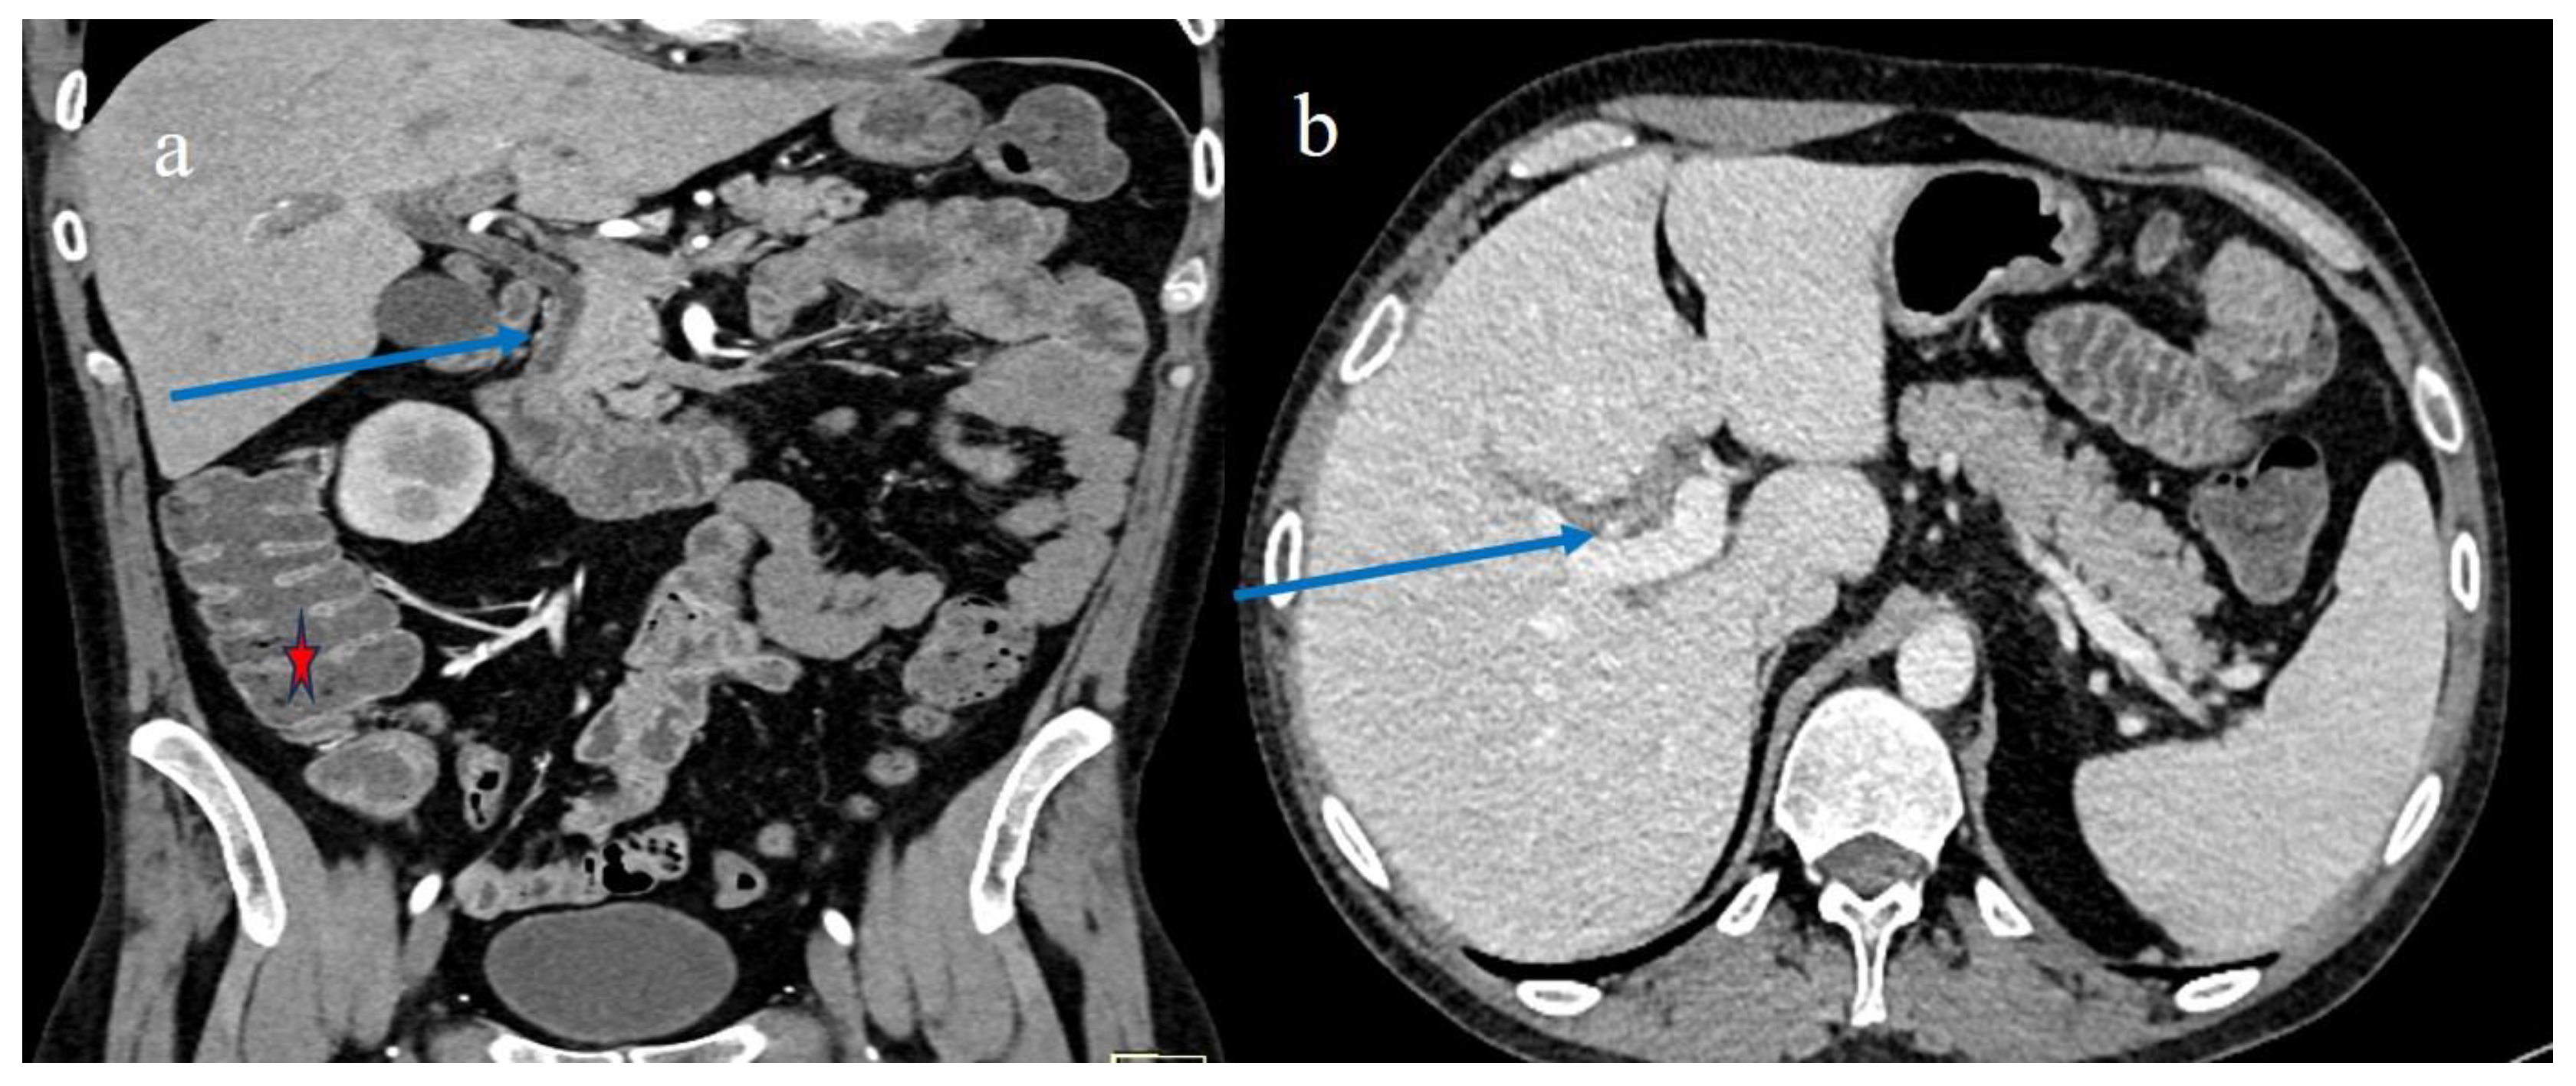

| 3 | P | P | Multisegmental thickness with stratified enhancement at the terminal ileus (on CECT control at 92 days). The CECT control at 129 days showed persistence of mild parietal thickness at terminal ileus and with mucosal enhancement | Diffuse parietal thickness with stratified enhancement (On CECT control at 92 days) The CECT control at 129 days showed colic fluid distension with mild diffuse mucosal enhancement | Diffuse comb sign, mild ascites, and poor reactive mesenteric lymph node | Hepatomegaly and mild gallbladder thickness |

| 4 | P | P | Intestinal diffuse homogeneous thickness with homogeneous mucosal enhancement (on CECT control at 66 days after the HSCT); diffuse small bowel involvement with increased parietal thickness on CECT control at 120 days | Appearance of multisegmental thickness on sigma and descending colon and stratified enhancement on transverse colon on the CT FU at 120 days | Diffuse comb sign and poor reactive mesenteric lymph node | Mild gallbladder thickness and persistence of biliary tract dilatation on follow-up CT |